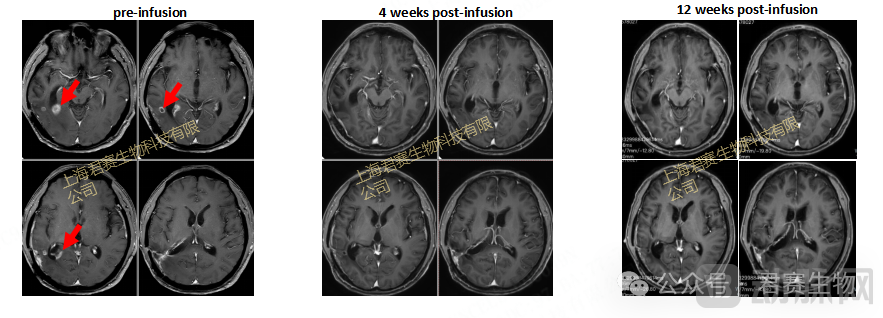

2023 年末,W先生和家属陷入绝望之际,命运的转机悄然降临。W 先生顺利加入 GC101 临床试验,接受 TIL 细胞回输治疗(细胞来源于其一年前手术取材培养)。回输后仅4 周,影像学显示其脑部肿瘤被完全清除,疗效评估为完全缓解(CR),后续再无复发,至今维持无瘤生存状态已超20个月。如今W先生早已摆脱了病床的束缚,重获新生,回归来之不易的正常生活。

患者磁共振影像(MRI)变化

截至目前,这一案例不仅刷新了复发性胶质母细胞瘤的生存纪录,更用鲜活的临床数据再次验证了TIL疗法的持久疗效,同时也为"早期取材,复发后回输TIL"的治疗策略提供了关键的临床证据,为无数身处绝境的实体瘤患者带来生之希望。